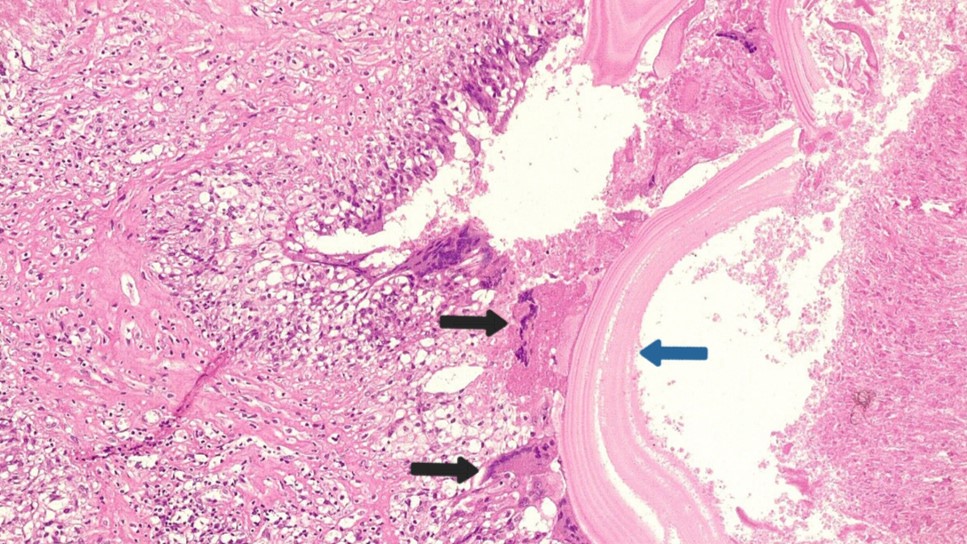

A total of 398 articles were identified through the search. After an initial review, 11 articles were excluded due to duplication and non-English language. The remaining 387 articles underwent title and abstract screening, during which 64 articles were excluded for not meeting the inclusion criteria. Consequently, 323 articles proceeded to full-text screening, and 93 were excluded due to unretrievable data, editorials, letters, or incomplete information. The remaining articles were then assessed for eligibility, resulting in 229 articles [1, 3, 4, 6-231] with 1,002 patients meeting the inclusion criteria and included in the study [Fig. 1].

Among the included studies, 217 (94.76%) were case reports, seven (3.06%) were cohort studies, three (1.31%) were case series, one (0.44%) was a cross-sectional study, and one (0.44%) was a randomized controlled trial (Table 1). Among the countries, Spain recorded the highest number of cases with 362 (36.13%), followed by China with 270 cases (26.95%) and Turkey with 128 cases (12.77%), collectively accounting for approximately 75% of the total reported cases (Table 2). In terms of continental distribution, Asia recorded 487 cases (48.60%), while Europe was not far behind with 460 cases (45.91%) (Table 3).